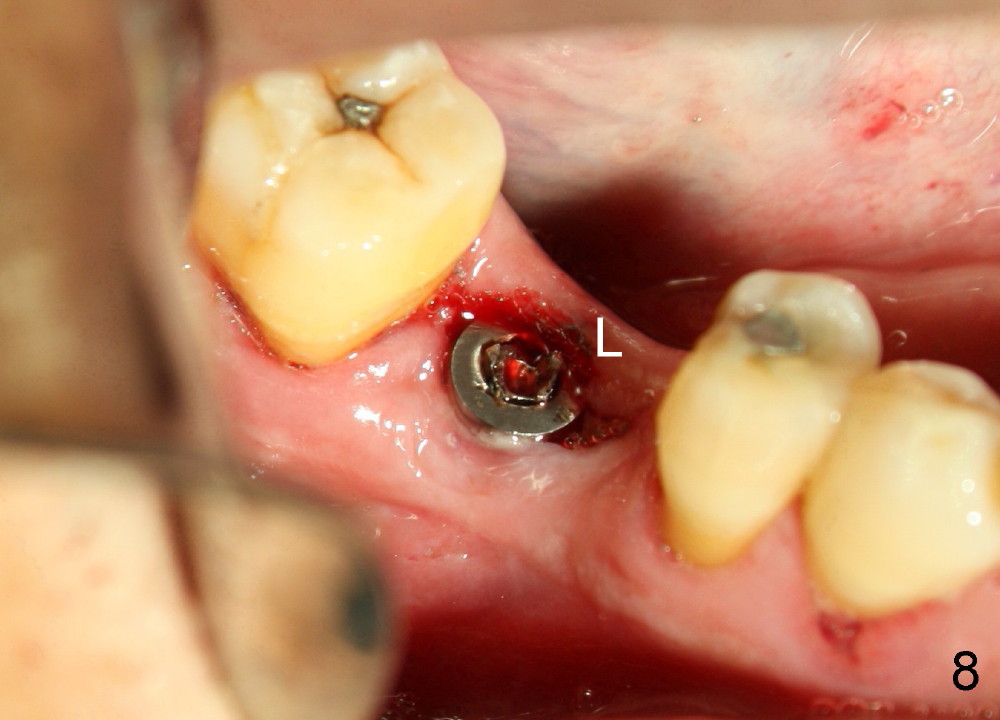

A 46-year-old man has severe periodontitis. The tooth #30 is complicated by incomplete root canal therapy (Fig.1,2). Three months after extraction (Fig.3-5: N: inferior alveolar canal), a 5x14 Tatum tapered implant is placed (Fig.6,7). The problem is that an implant driver is fractured (D in Fig.7), while the implant is being torqued. It takes time and effort to remove the fractured driver, but the implant is solid. The healing screw is placed without difficulty (Fig.8). Since the implant is placed lower than the lingual gingiva (L in Fig.9), a healing cuff is placed 1.5 months after implant placement (Fig. 10 and 11: C) to push the lingual gingiva down. The X-ray appears to show lower bone density around the implant (bone necrosis?), although the implant has no mobility at all. Since the implant is so solid, can we load it, two months after surgery? The lingual gingiva is now lower than the healing cuff (not shown). CT is scheduled to be taken tomorrow. Thanks.